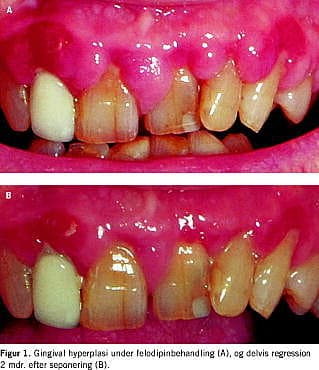

En 69-årig mand, der havde haft hypertension i tyve år og type 2-diabetes i syv år, klagede over hævet og irriteret tandkød 7 mdr. efter påbegyndt felodipinbehandling. Objektivt sås dårlig mundhygiejne, parodontitis marginalis profunda samt erytematøs og fibrotisk gingivalhyperplasi (Figur 1A ). Patienten havde nefropati med creatinin på 140 μmol/l og U-albumin/creatinin-ratio på 40 mg/mmol. Der var ingen diabetiske øjenbaggrundsforandringer. Diabetesreguleringen var god med HbA1c på 6,7%. Patienten var i antihypertensivbehandling med felodipin 10 mg, candesartan 16 mg, metoprolol 200 mg og furosemid 80 mg. Desuden blev der givet simvastatin, allopurinol, kaliumklorid, magnyl, calciumkarbonat, D-vitamin og insulin. Felodipin blev erstattet med prazocin, hvorefter den gingivale hyperplasi delvist regredierede over de følgende 2 mdr. (Figur 1B ). Patienten blev tilbudt parodontosebehandling og fjernelse af den persisterende hyperplasi i regio 7,6+.

Summary Gingival hyperplasia and calcium antagonists Ugeskr Læger 2004;166:3828-3829 A photo-documented case of gingival hyperplasia induced by felodipine and its partial regression after two months of withdrawal is presented.